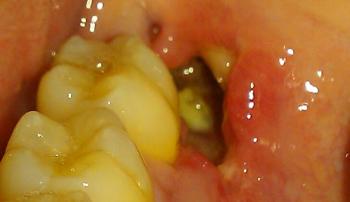

I see a dark, fairly deep socket behind the last visible molar (the extraction site).

No obvious pus or large swelling visible in the photo and you report no pain — both reassuring.

Surrounding teeth look intact. Photo lighting/angle limits how much I can see (I can’t check bleeding under the gum or feel for mobility).

Bottom line: this looks like a normal 7-day post-extraction socket (deep appearance from the clot/early granulation tissue) rather than an acute complication — but a picture can’t replace a clinical exam.